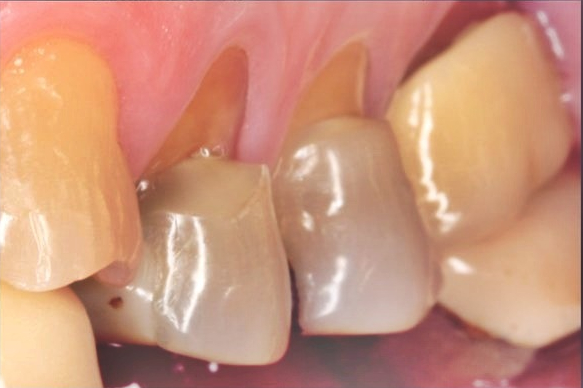

치경부 마모증(cervical abrasion)은

➡ 치경부가 마모되면서 'V자' 모양으로

깎이고 파이는 구강 질환을 얘기합니다.

심할 경우, 치아 내부 속

뿌리와 신경이 바깥으로 드러나며

시린 증상은 물론, 통증을

계속해서 일으키곤 하는데요

시간이 지날 수록 마모가 심해져

치아가 뚝! 하고 부러질 위험이 있어